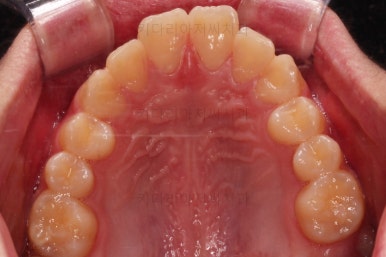

치료 끝!

전체적인 교정을 하지 않았기 때문에 완벽히 디테일을 맞추긴 힘들었지만 충분히 기능을 할 수 있게끔 위치를 바로잡아 주었어요.

총 치료기간은 단 5개월!

부산연산동사랑니발치 치료 전후를 비교해 보겠습니다.

5개월이라는 매우 짧은 기간인데 정확한 치료계획과 고난이도 테크닉으로 매복 사랑니도 발치하고 매복된 어금니도 바로 세워서 잘 사용할 수 있게끔 해드렸습니다.